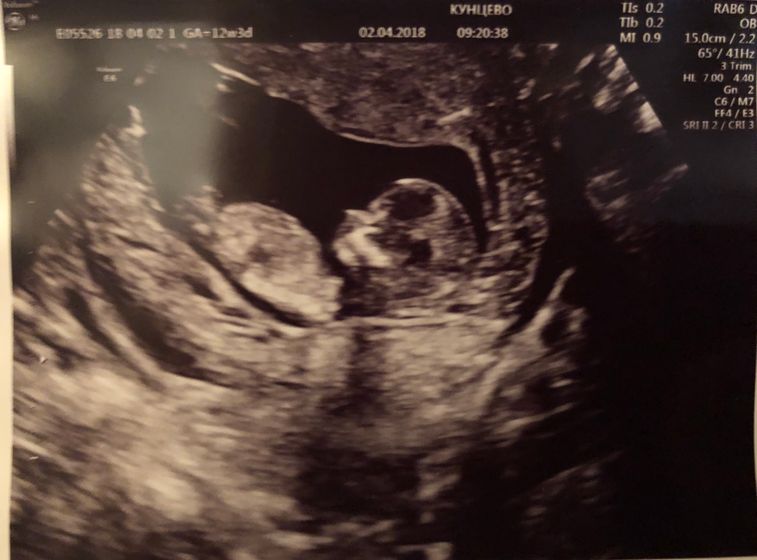

Вот вчера и прошёл мой первый скрининг?

Смотрите какую красоту нам сделали?

Малыш ещё и танцевал для нас)) и эти танцы записали на диск???

Сказали, что так скорее всего выглядят девчонки, но может быть и парень...)хотим конечно парня, но и дочурочке будем безумно рады❤️